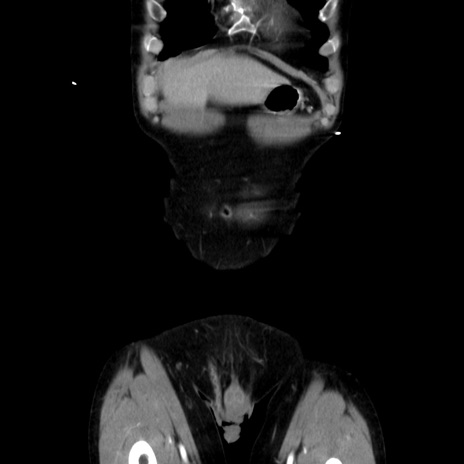

症例37(冠状断像)

【症例】40歳代 男性

【主訴】腹痛

【現病歴】4時間ほど前に電車に乗車中に臍部上より腹痛出現。徐々に増悪し起立困難となり、救急外来受診。生ものは数日食べていない。今朝お雑煮を食べた。

【身体所見】BT 36.8℃、BP 117/84mmHg、HR 91/min、SpO2 97%、苦悶様、腹部:臍上部広範囲圧痛あり、反跳痛±

【データ】WBC 8100、CRP 0.03